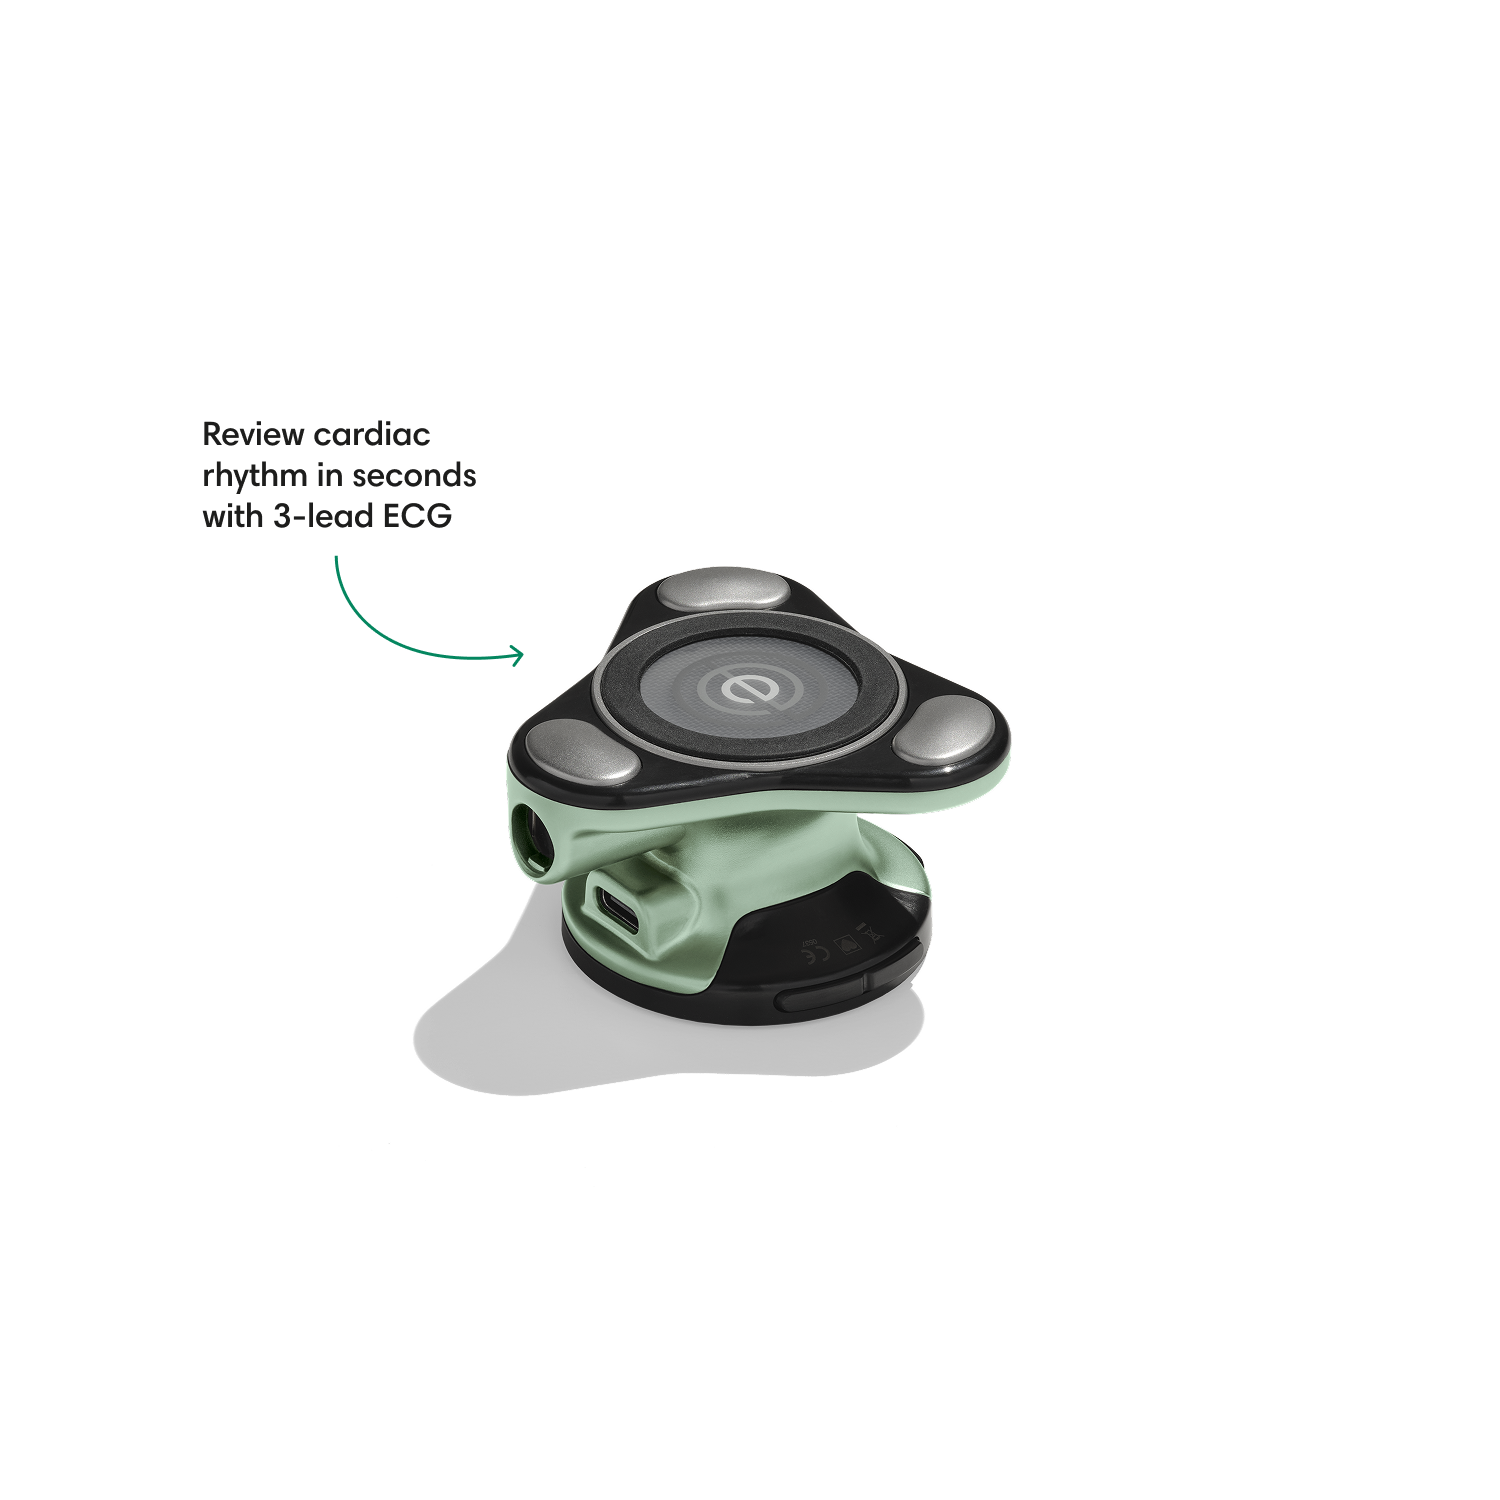

Go beyond sound alone.

For the first time ever, measure heart rate, visualize 3-lead ECG, and see detection results — right on a built-in, full-color display.